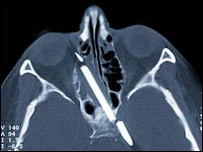

दिमाग में धंसी पेंसिल

एक हादसे में पेंसिल वेगनर की दाहिनी आँख के कुछ ऊपर मस्तिष्क तक धंस गई थी

इस पेंसिल का कुछ हिस्सा दाहिनी आँख के कुछ ऊपर मस्तिष्क तक धंस गया था.

मस्तिष्क में फंसी इस पेंसिल की लंबाई कोई आठ सेंटीमीटर थी और आँख का संवेदनशील हिस्सा इससे होने वाले नुक़सान से बाल-बाल बचा था.